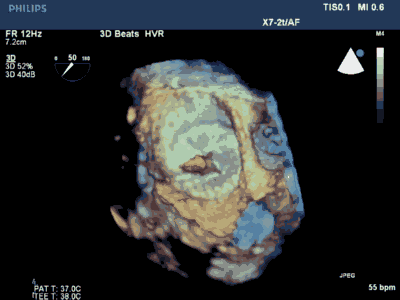

3. 经右侧股静脉置入SL1鞘管,沿鞘管送入房间隔穿刺针,食道超声下见左心耳血栓

4. 超声指导下成功行房间隔穿刺,将鞘管推进至左房后予肝素7000U,SL1 导丝送左房后,超声下测左心耳开口大小后选用LAmbre 左心耳封堵器(20-26mm)

5. 超声及造影下见封堵器放置位置良好,二尖瓣及肺静脉段未见影响,测试位置固定后释放封堵器